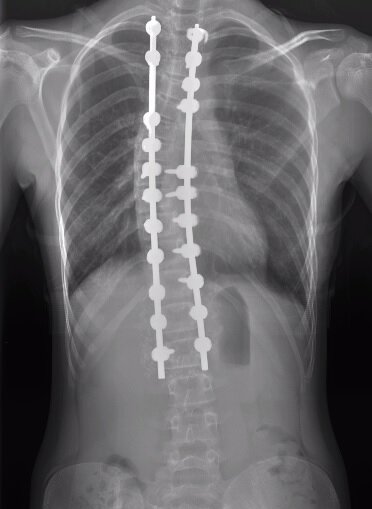

Susan's spine after surgery

Susan would be in the hospital for four days. On the first day, she had the operation. Murphy described what he and his team did. "Susan's spine was twisted to the side, so we made an incision and put screws into the bone segments and used rods to contour the shape of her spine and bring it into corrected position. We then fused the spine so that the curve could not progress into her adult life."

Murphy was careful not to overdo the procedure. "We fuse as few levels as we can, because we want to make sure kids are still flexible and get back to the activities they love."